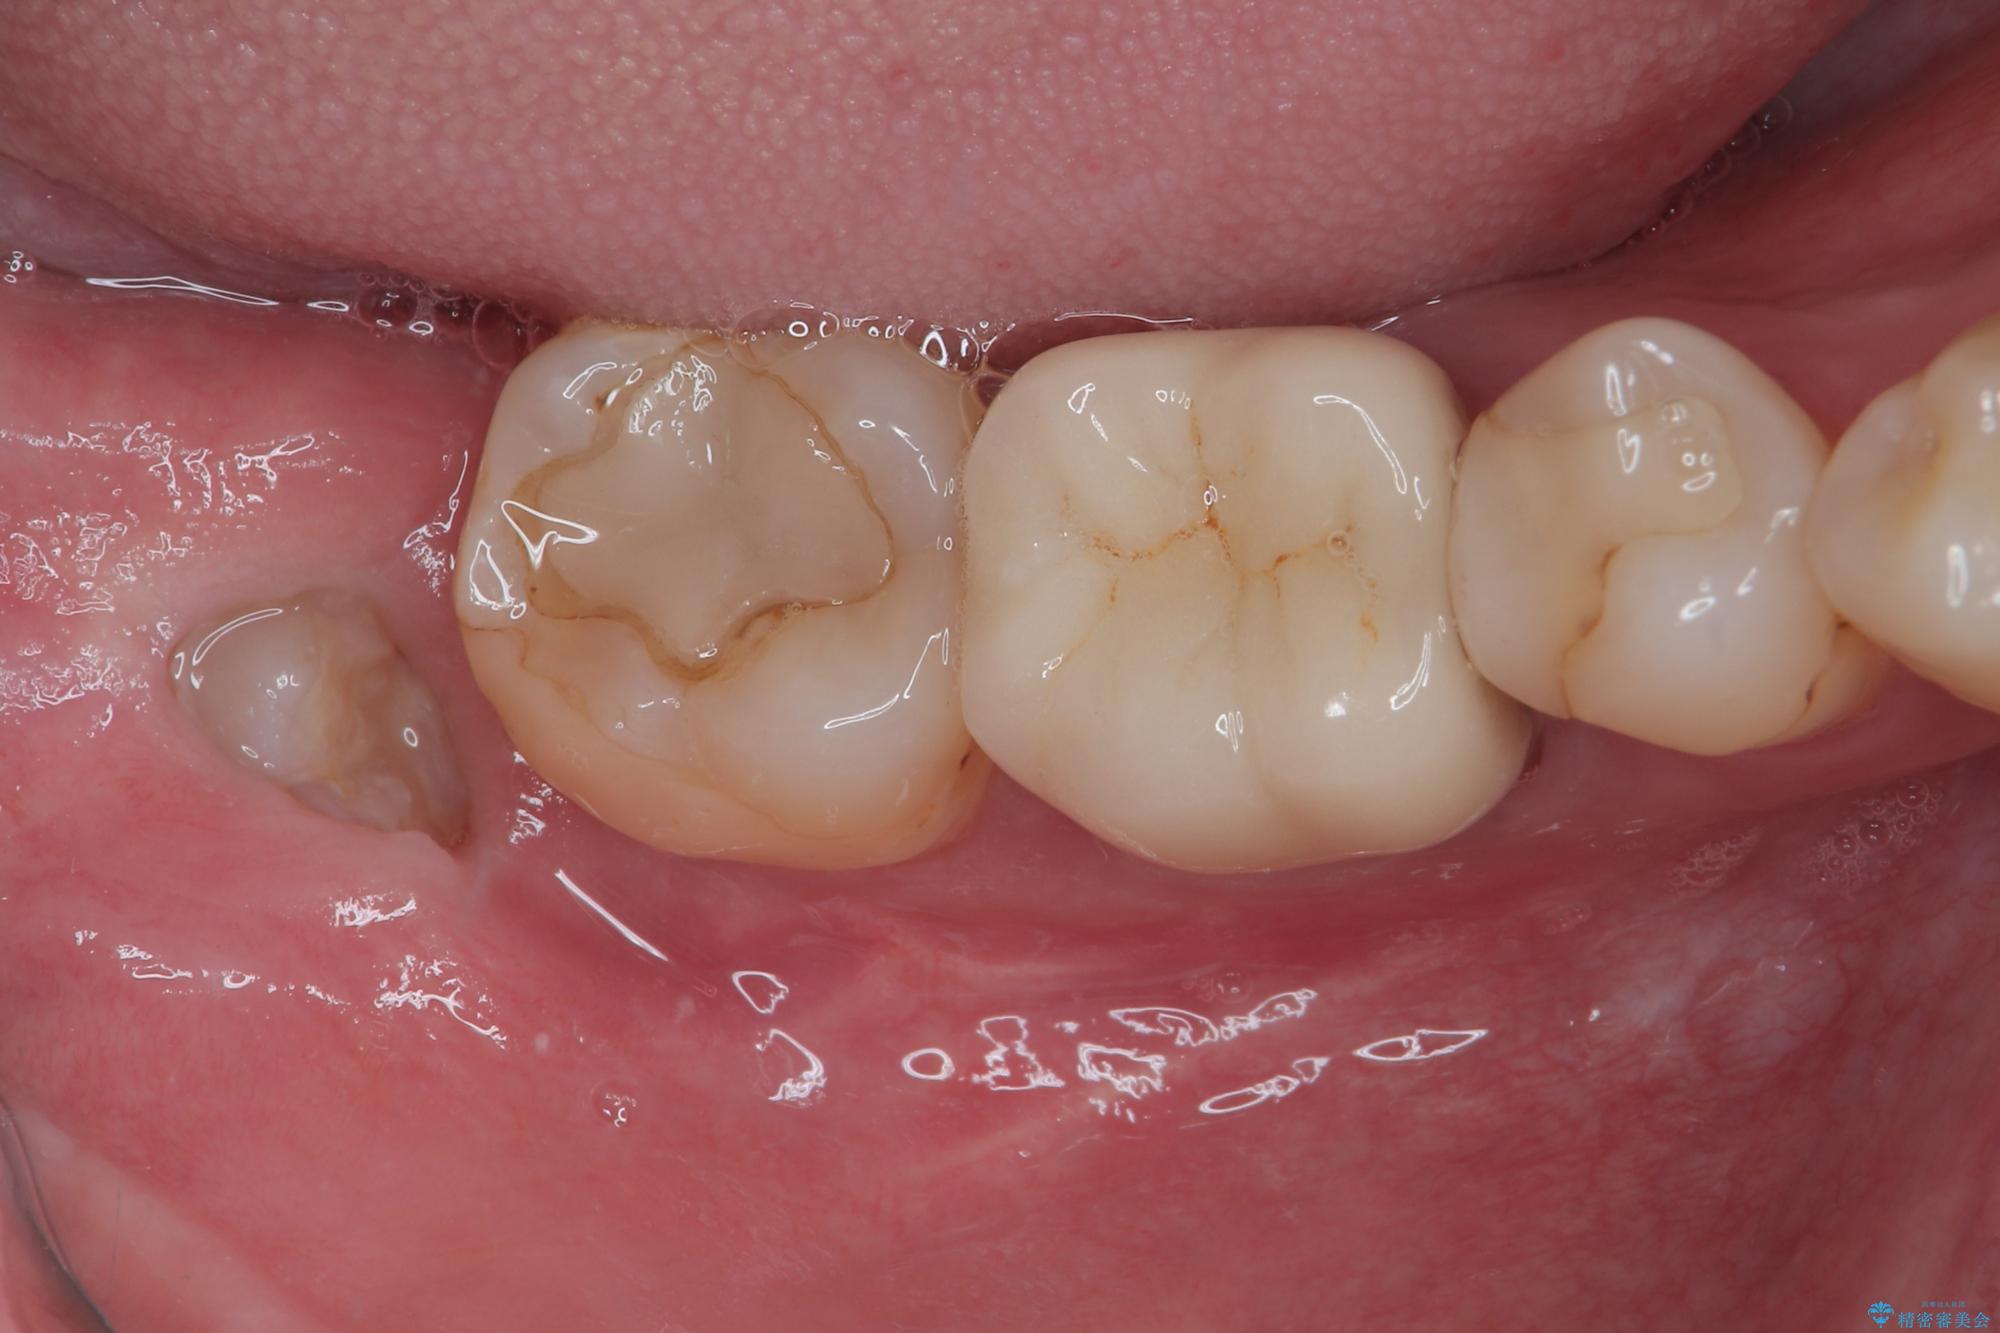

一週間後に抜糸を行いました。